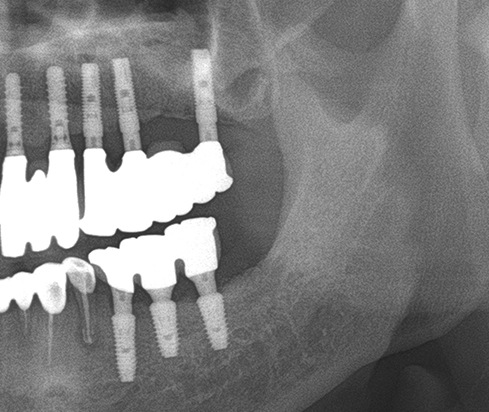

Another clinical case using non resorbable membrane and bone tac

• Another clinical case using  non resorbable membrane and bone tac 1